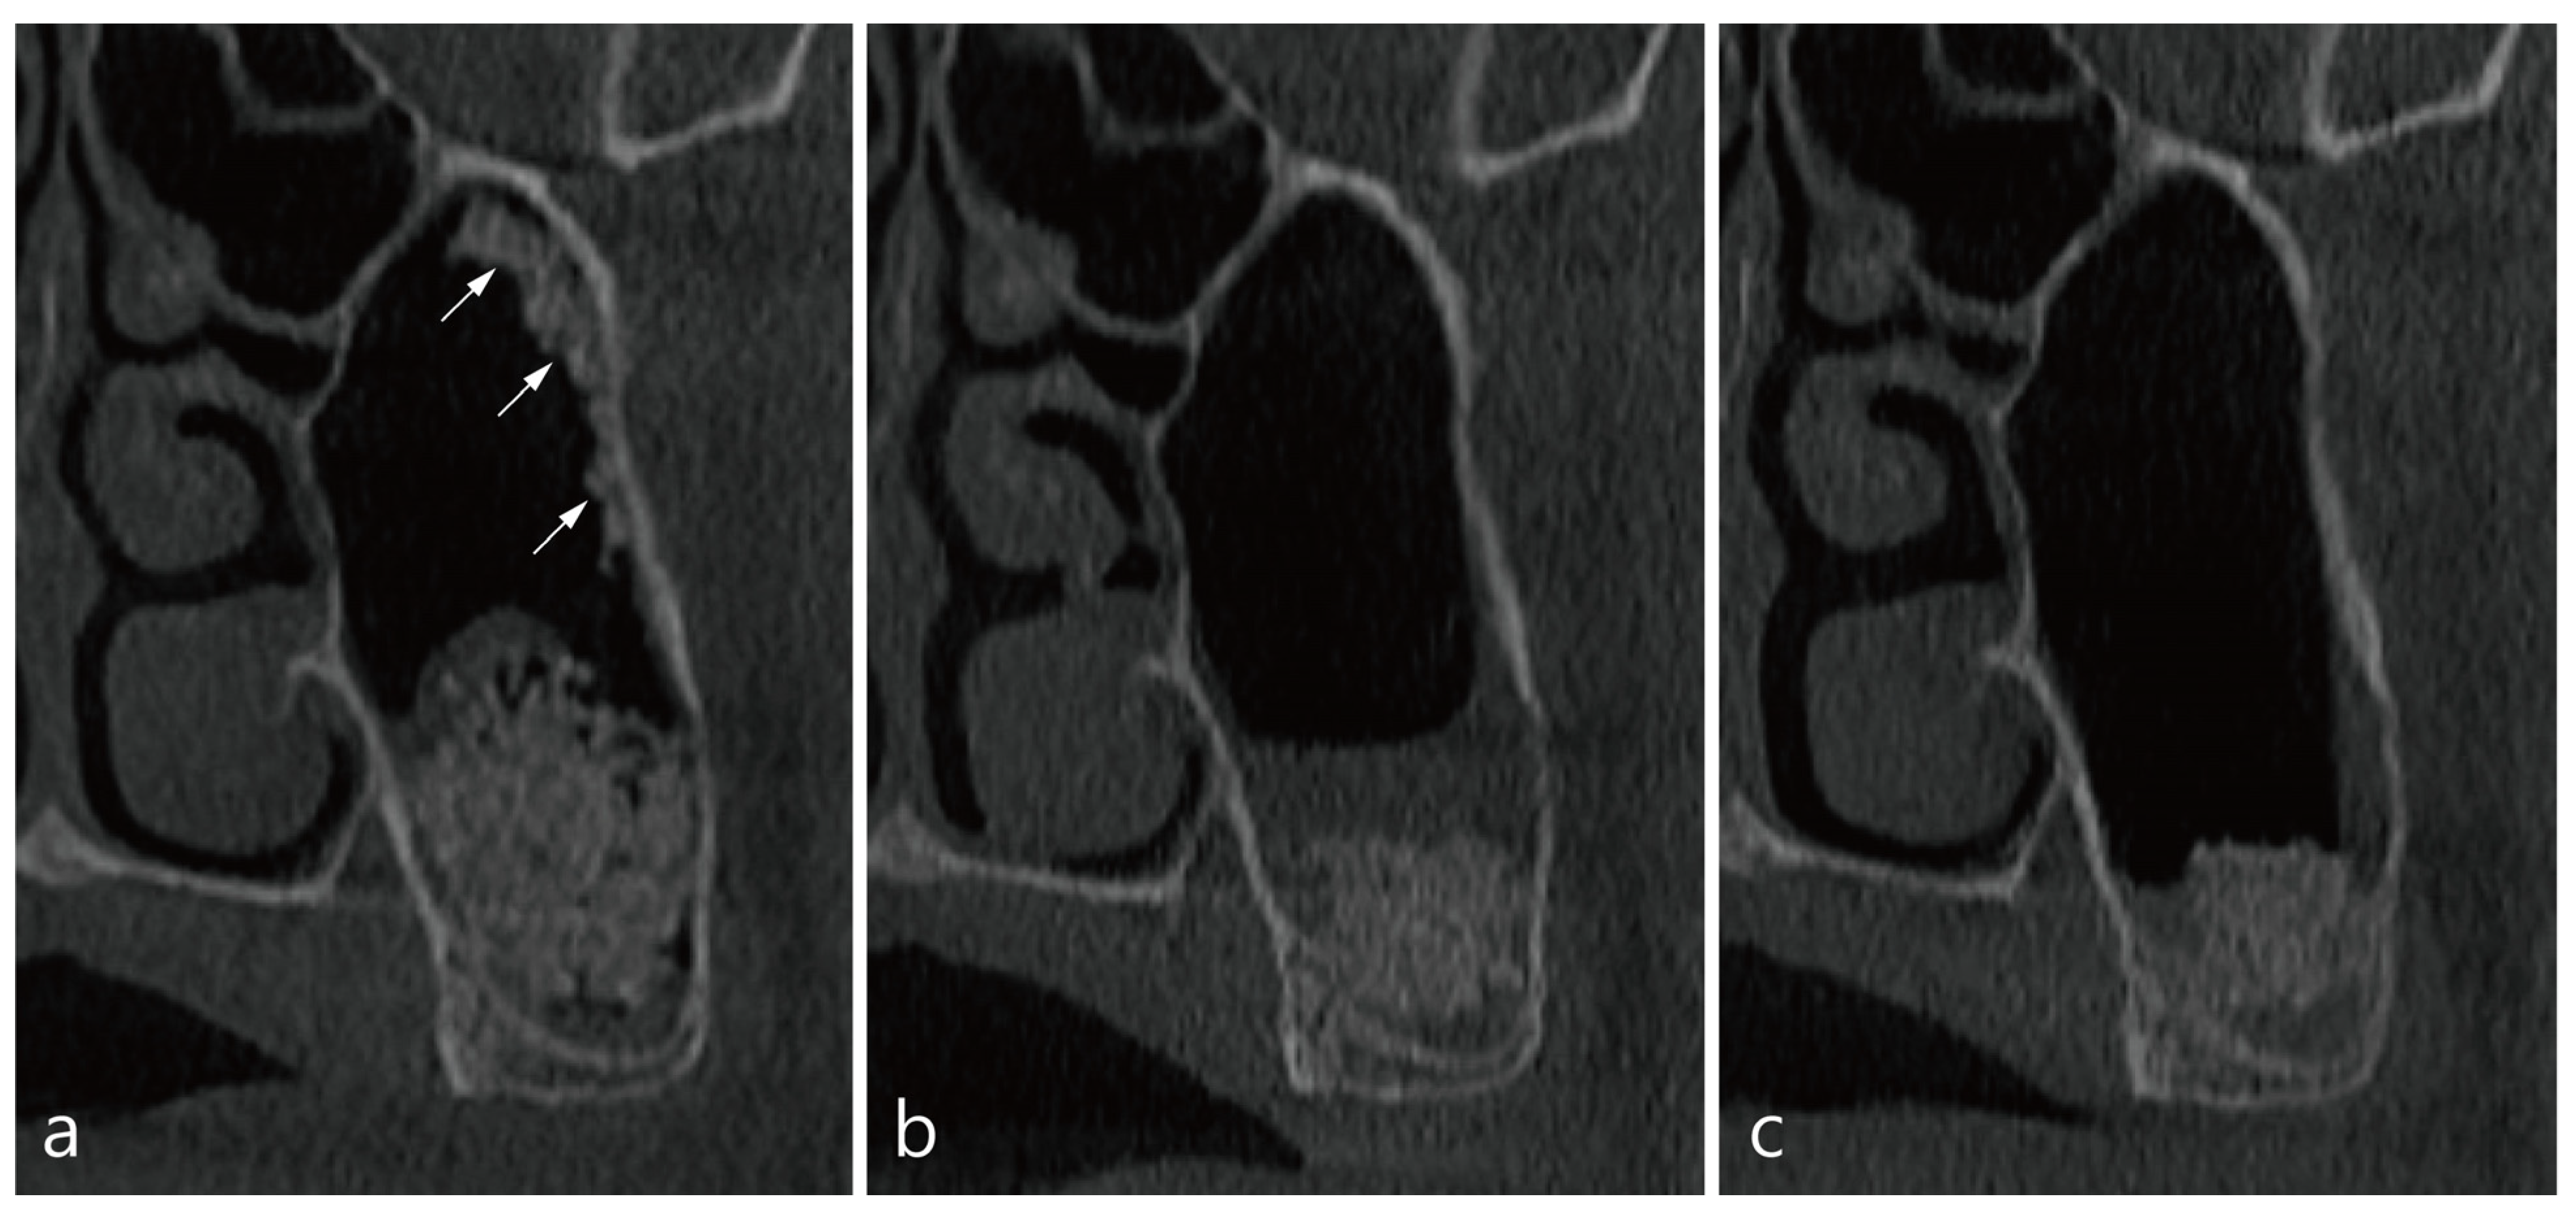

5. Case 3